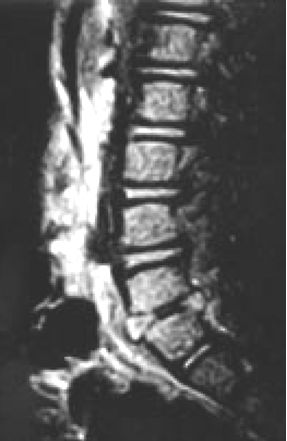

Resonancia Magnética de columna al ingreso.

La resonancia magnética de la columna vertebral es el estudio de elección, ya que puede detectar discitis temprana, y excluyen los tumores de la columna vertebral.